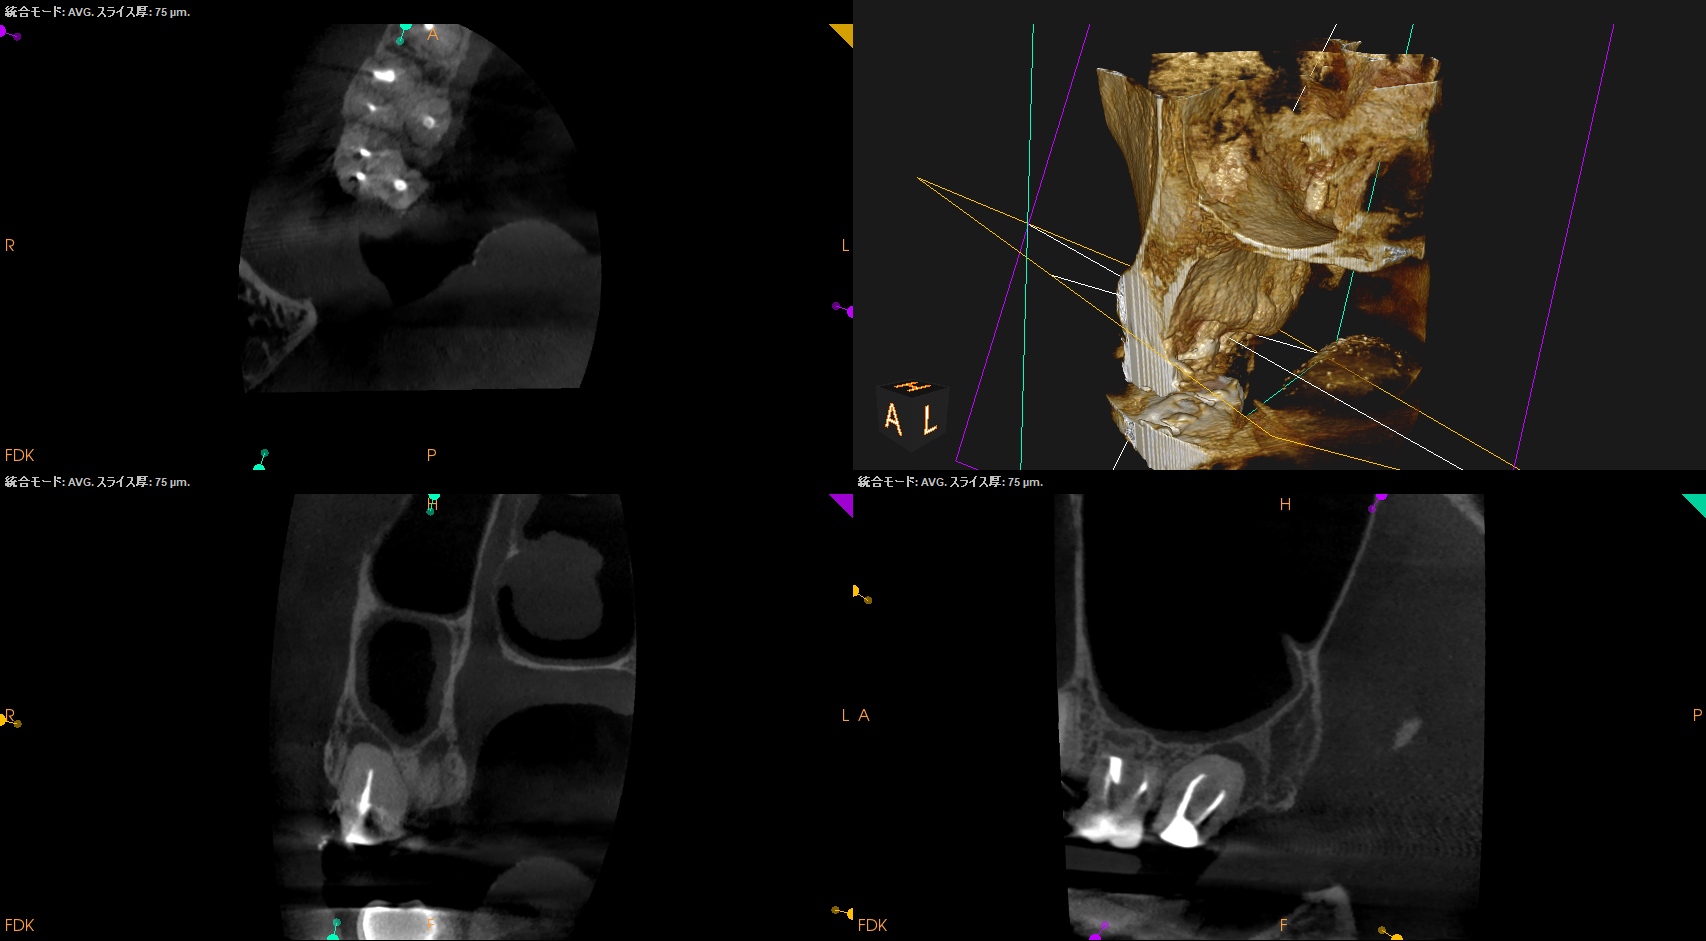

術後に口腔内PA, CBCTも撮影した。

MB

DB

P

ということで問題が客観的にないことがわかる。